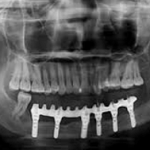

The conventional approach is completely based on the expertise and experience of the clinician. It includes simultaneous resection of the mandibular pathology as well as the harvesting of the fibular graft. This is done on the basis of manual measurements, making it not 100% accurate. The resection is then followed by the surgical reconstruction of the mandible by harvesting the fibular graft (image 3). Before the placement of implants the patient is asked to wait for a period of 3-5 months for the graft to get accepted.

After the acceptance and healing of the graft, a second surgery is conducted to place the implants; followed by another waiting period of 3-6 months for the osseointegration of the implants. The process of fabrication for the prosthesis beings after this; thereby increasing the time frame required for the complete rehabilitation to 9-12 months.

Drawbacks of conventional approach

Long waiting period till satisfying function and esthetics are achieved.

Formation of a thick layer of soft tissue post the first surgery hampers the placement of implants; in such cases “Debulking” of the soft tissue is necessary.

Manual measurements used for resection make it difficult to reach optimal positioning of implants.

Each surgical intervention increases the risk of infection.

A study of 56 patients has reported 92% implant success versus only 42.9% prosthetic success. The reasons proposed by the authors are patient’s poor cooperation (30.4%), tumour recurrence

(14.3%) and surgery-related factors (10.8%) in which the authors include both implant failure and an unfavourable relationship between the maxilla and the reconstructed mandible. One should

consider that a high implant osseointegration rate is not significant if the functional prosthetic result is bad10.

Thus from this study it is inferred that the success of such cases is predicted from the stand point of final occlusion achieved and duration needed for the complete reconstruction; which necessitates the use of digital methods.